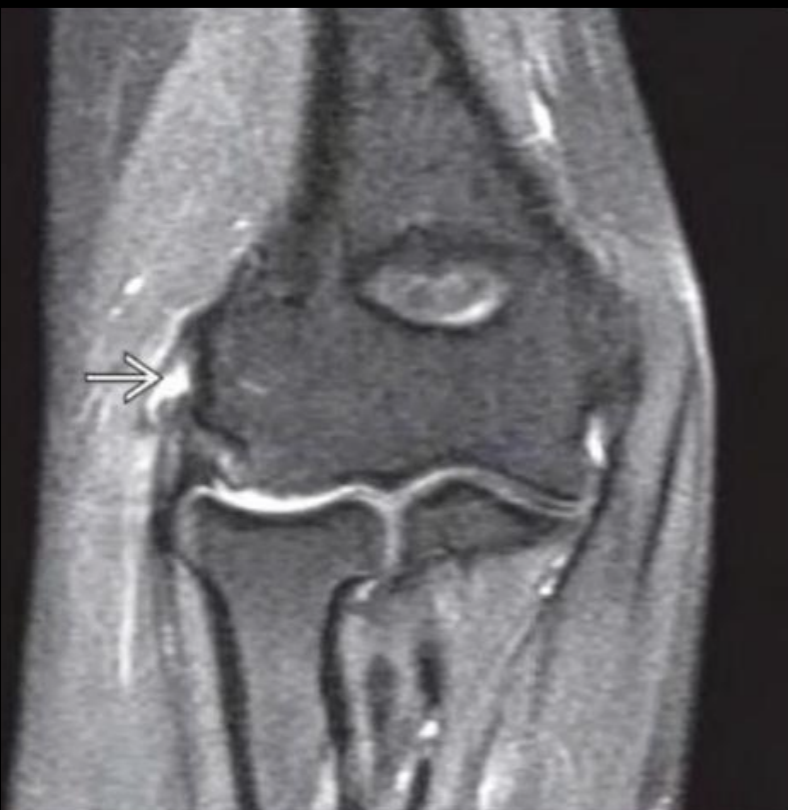

RM en epicondilitis

Hiperintensidad y engrosámiento del tendon

Lesiones asociadas

A

Epicondilitis